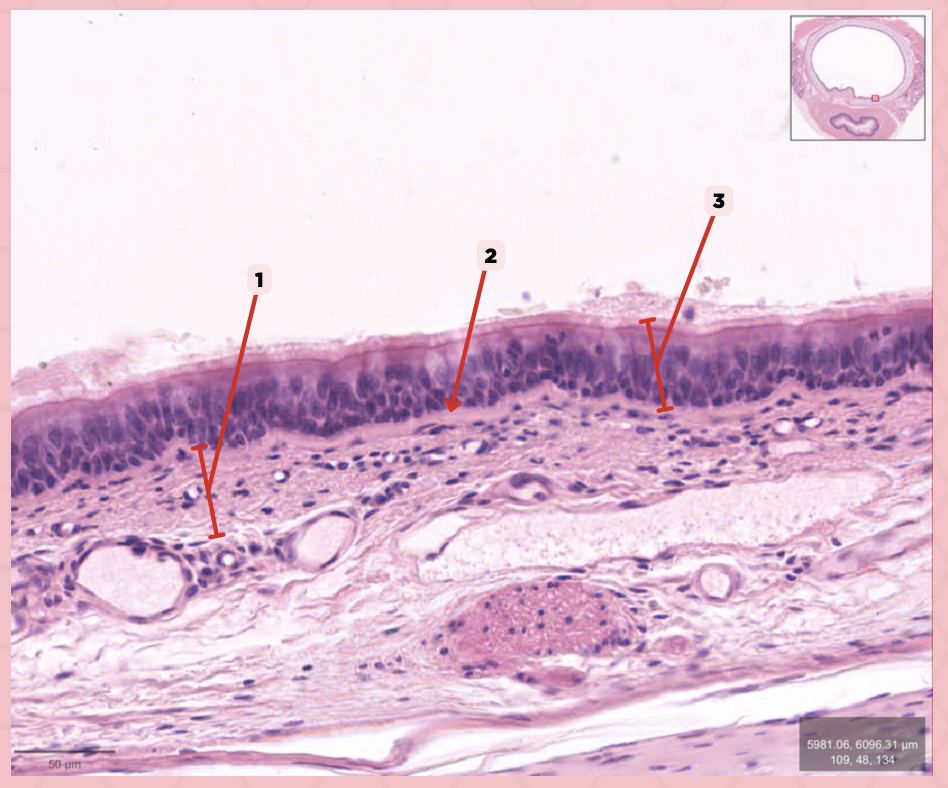

Respiratory Epithelium

Identify the structure labeled as 1.

Lamina Propria

Identify the structure labeled as 2.

Bony spicule

Identify the structure labeled as 3.

Respiratory Epithelium

What epithelium lines this structure?